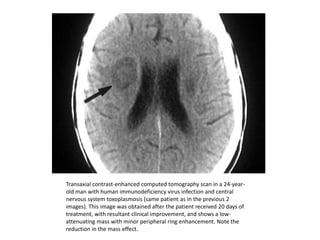

Transaxial contrast-enhanced computed tomography scan in a 24-year-

old man with human immunodeficiency virus infection and central

nervous system toxoplasmosis (same patient as in the previous 2

images). This image was obtained after the patient received 20 days of

treatment, with resultant clinical improvement, and shows a low-

attenuating mass with minor peripheral ring enhancement. Note the

reduction in the mass effect.

Transaxial contrast-enhanced computedtomography scan in a 24-year- old man with human immunodeficiency virus infection and central nervous system toxoplasmosis (same patient as in the previous 2 images). This image was obtained after the patient received 20 days of treatment, with resultant clinical improvement, and shows a low- attenuating mass with minor peripheral ring enhancement. Note the reduction in the mass effect.